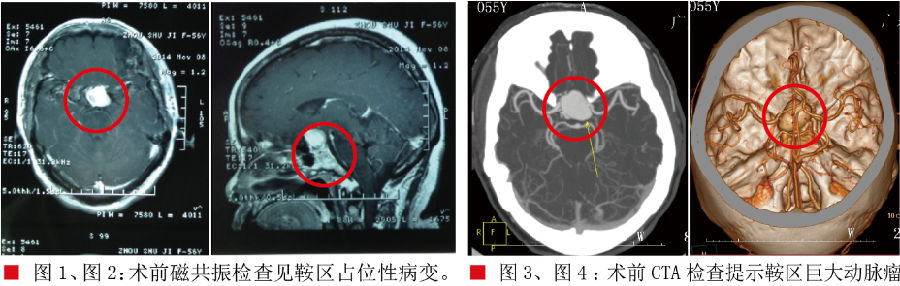

患者两月前无明显诱因出现头痛,伴有头晕,头痛呈阵发性,主要位于额部,偶尔伴有麻木感,休息后可自行缓解。就诊当地医院行头颅MRT示:鞍区占位性病变,考虑垂体瘤可能性大,建议患者行经鼻蝶垂体瘤切除术,患者为了得到更专业的治疗,就诊我院,门诊以“鞍区占位性病变,考虑垂体瘤可能性大”收治入院。入院查体:生命体征平稳,神志清楚,对答切题。双瞳孔等大同圆,直径2.5mm,对光反射灵敏,视力,左侧:1米前数指,右侧0.4,双侧颞侧偏盲,双侧眼球活动自如,四肢肌力5级,肌张力正常,全生理反射存在,病理征未引出。入院诊断:鞍区占位性病变,垂体瘤?脑膜瘤?动脉瘤?完善相关检查行CTA提示:鞍区巨大动脉瘤;完善检查全麻下为患者行“鞍区巨大动脉瘤栓塞术”,患者术后7天出院;出院时查体:神志清楚,对答切题。双瞳孔等大同圆,直径2.5mm,对光反射灵敏,视力,左侧:3米前数指,右侧0.5,双侧颞侧偏盲,较术前有所好转,双侧眼球活动自如,四肢肌力5级,肌张力正常,全生理反射存在,病理征未引出。